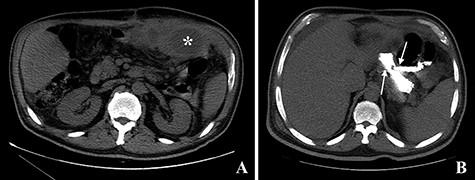

The computed tomography (CT) scan with oral contrast revealed a GGF (see Fig. 1). The upper gastrointestinal endoscopy confirmed a GGF and also demonstrated a stenosis of the gastro-jejunal anastomosis (GJA) (see Fig. 2).

Computed tomography with intravenous contrast images demonstrating a gastro-gastric fistula (arrows). A: axial reconstruction; B: sagittal reconstruction.